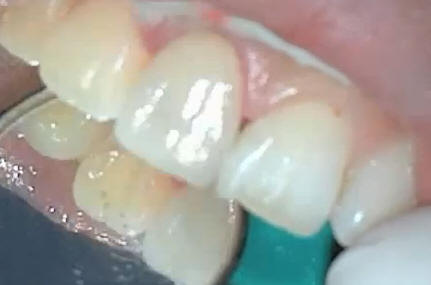

La corona alúmina

terminada se prueba nuevamente para ver tono y matiz

correcto |

Cementar con resina con

Aislar y secar la zona

para el cementado, dejar endurecer para luego quitar los

excesos de material sin dañar los tejidos blandos. Corona de

alúmina instalada. |